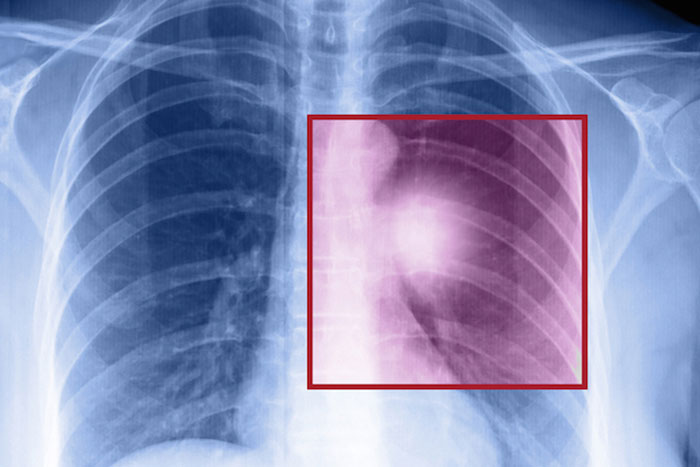

今回、人体に無害な光(近赤外線)を当ててがん細胞を壊す新しい治療法を米国立保健研究所(NIH)の小林久隆・主任研究員らが開発し、患者で効き目を調べる治験(臨床試験)を近く始める。光を受けると熱を出す特殊な化学物質をがん細胞の表面に結びつけ、がんだけを熱で狙い撃ちする。

近赤外線は放射線や陽子線と違い正常細胞には無害であるし、取り扱いが容易である。標的となるがん細胞に対しては抗体を使い、がん細胞に結びついた抗体は近赤外線に反応してがん細胞を効率的に攻撃するなどの工夫を取り入れた。